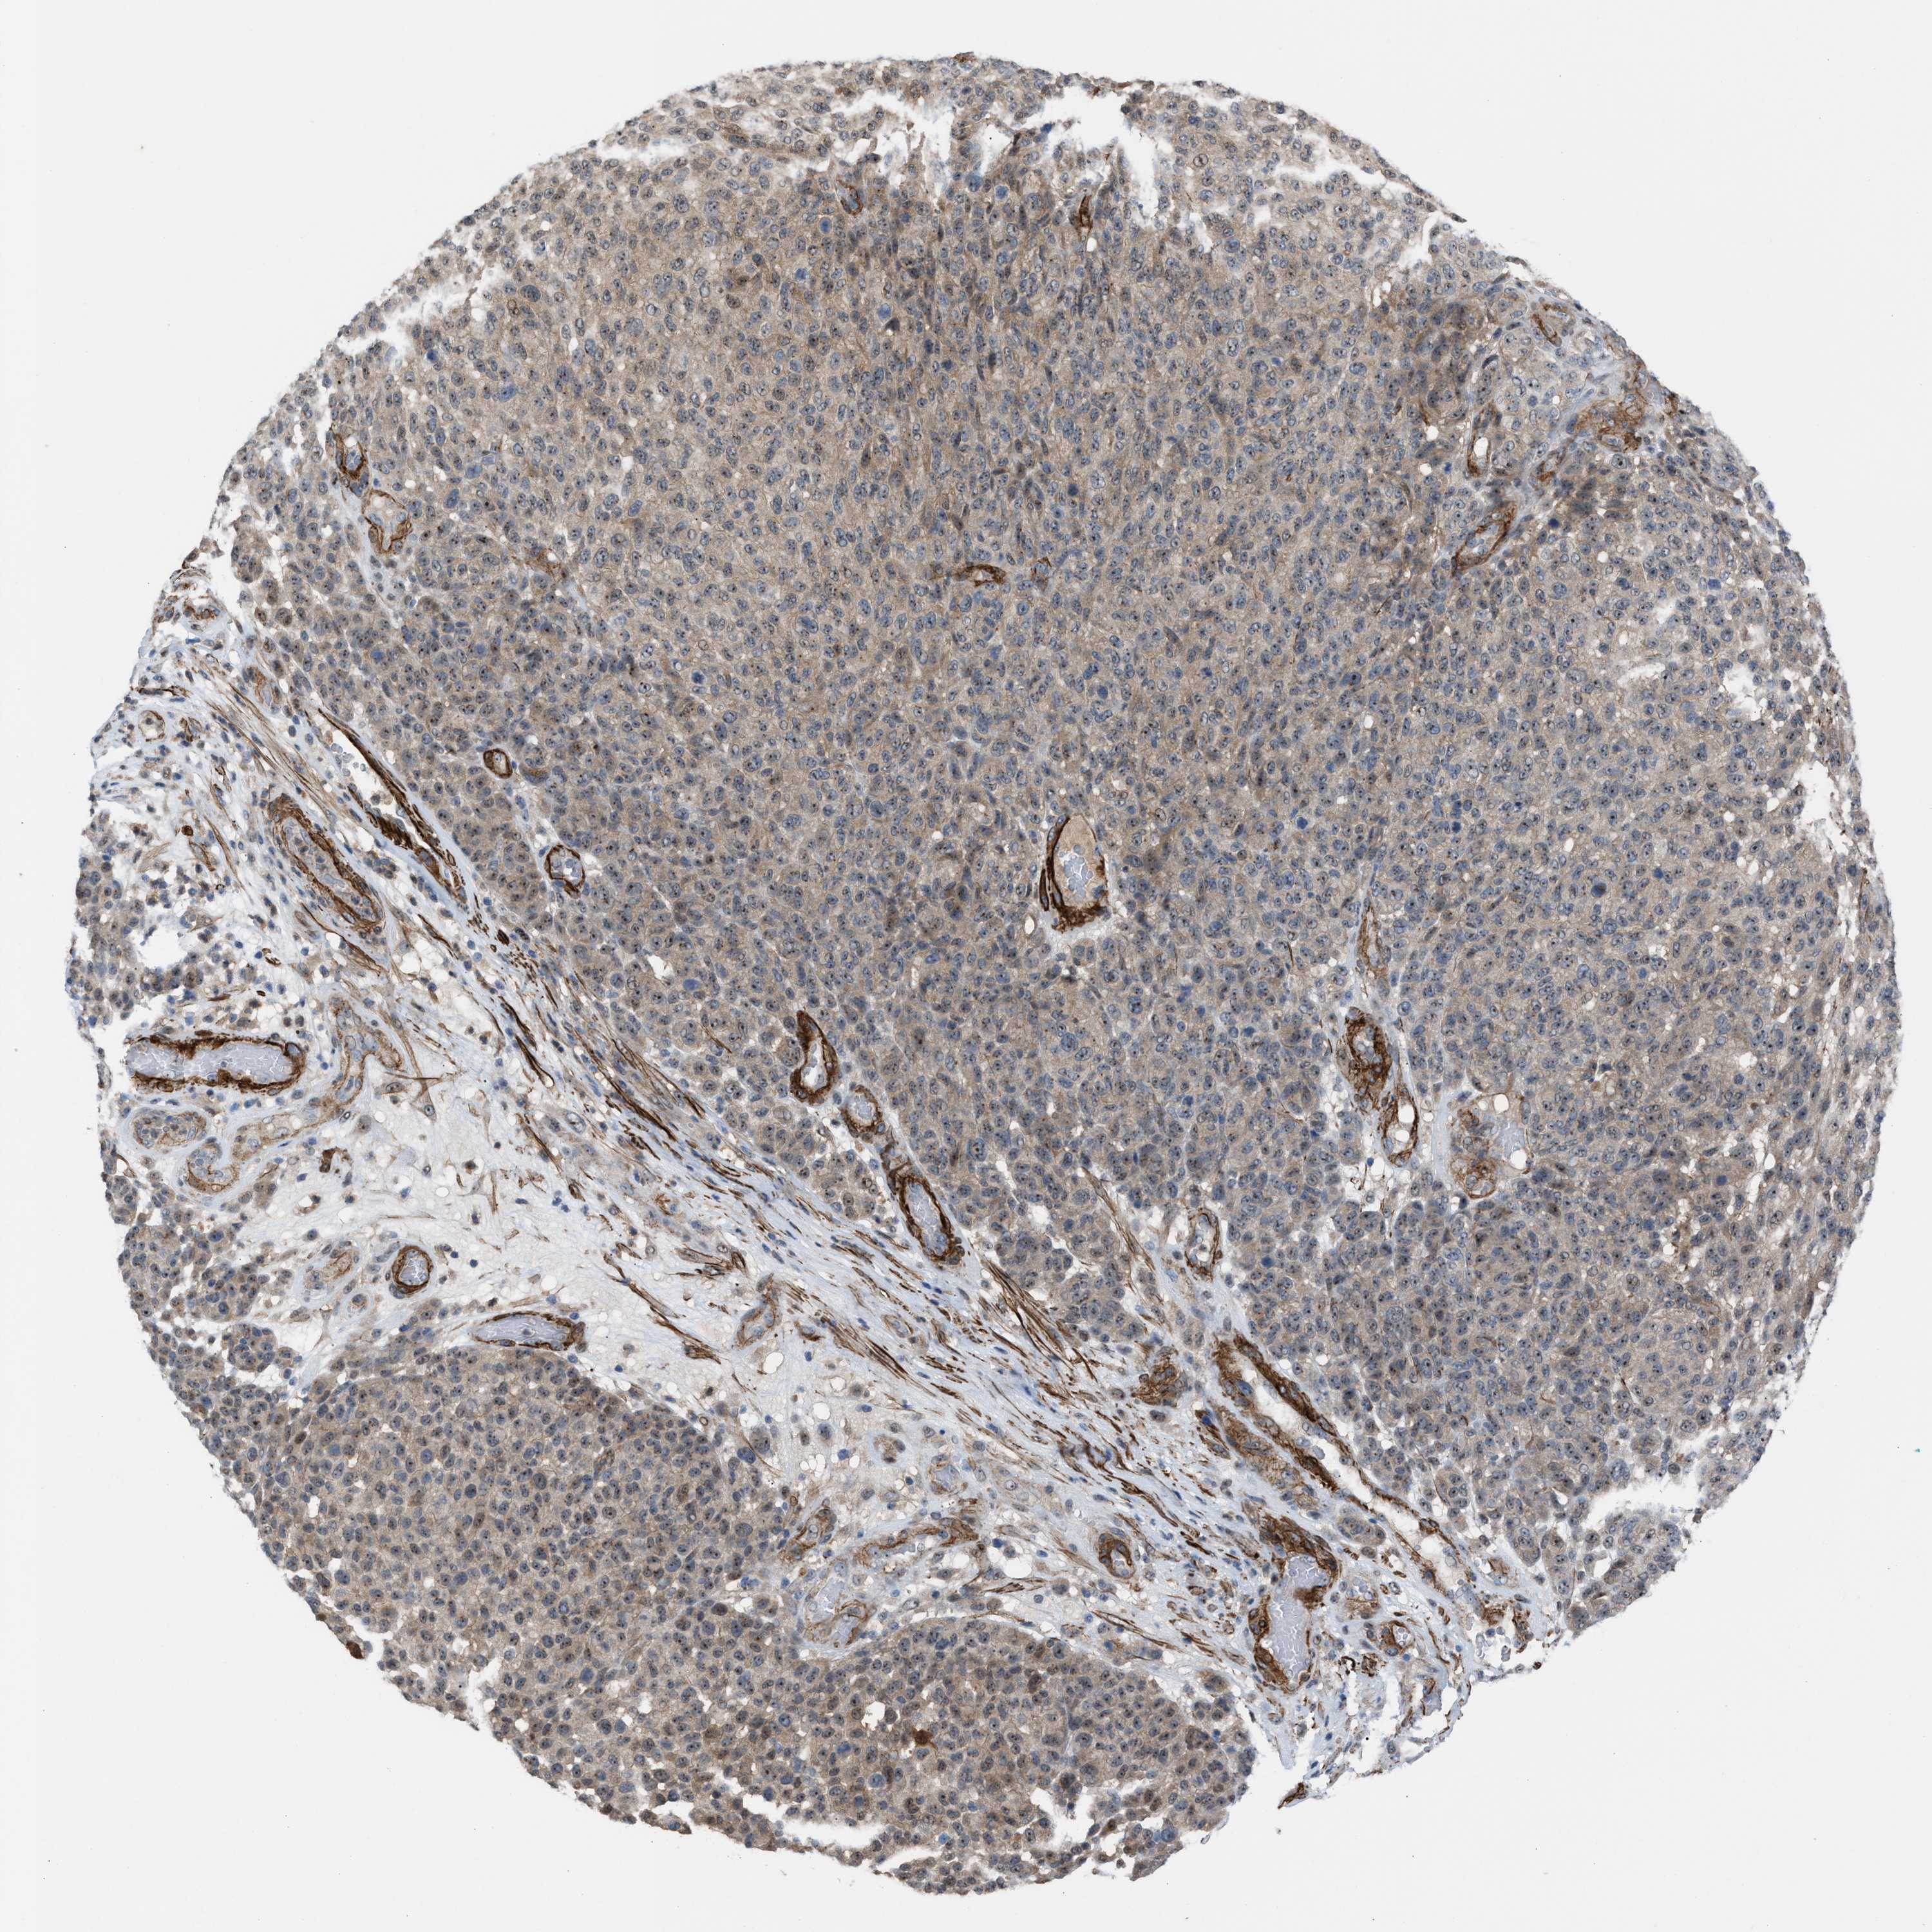

MELANOMA - Protein expressioni

A mouse-over function shows sample information and annotation data. Click on an image to view it in a full screen mode. Samples can be filtered based on level of antibody staining by selecting one or several of the following categories: high, medium, low and not detected. The assay and annotation is described here.

Note that samples used for immunohistochemistry by the Human Protein Atlas do not correspond to samples in the TCGA dataset.

Antibody stainingi

Antibody staining in the annotated cell types in the current human tissue is reported as not detected, low, medium, or high, based on conventional immunohistochemistry profiling in selected tissues. This score is based on the combination of the staining intensity and fraction of stained cells.

Each image is clickable and will lead to virtual microscopy that enables deeper exploration of all samples and also displays staining intensity scores, fraction scores and subcellular localization as well as patient and tissue information for each sample.

Antibody HPA021283

Antibody HPA021332

Staining

High

Medium

Low

Not detected

Intensity

Strong

Moderate

Weak

Negative

Quantity

>75%

75%-25%

<25%

None

Location

Nuclear

Cytoplasmic/membranous

Cytoplasmic/membranous,nuclear

Malignant melanoma, NOS

Malignant melanoma, Metastatic site